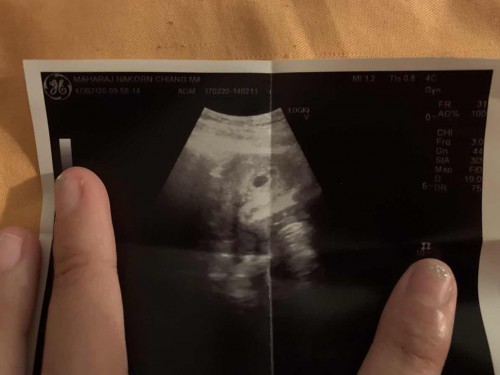

5สัปดาห์ค่ะ